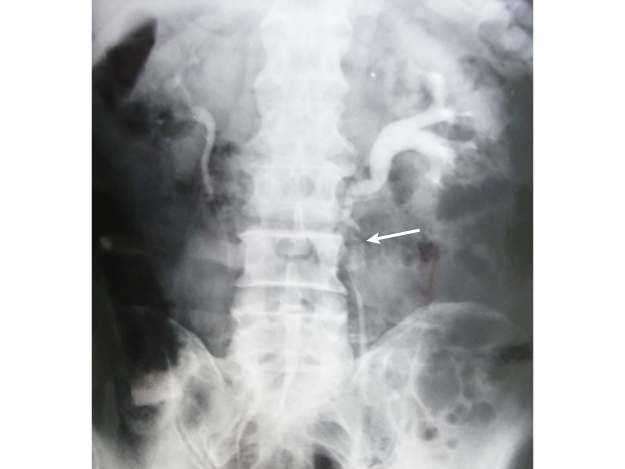

• 水腎症

図

人工血管置換術後に左尿管圧迫狭窄による水腎症

腹部大動脈瘤に対する人工血管置換術後、人工血管との交差部で左尿管の圧迫狭窄がおこり水腎症が発生